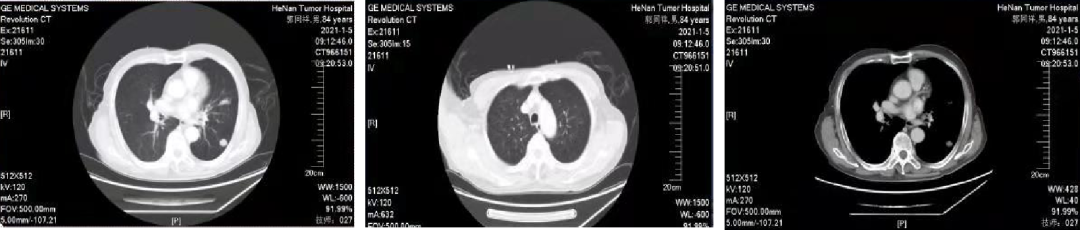

02 初诊病史

诊断:直肠腺癌双肺转移IV期,KRAS 突变型,MSS。高龄,患者及家属无手术意愿,全身系统治疗。

03 治疗方案:全身系统治疗

一线治疗

2021.01.14 始行“卡培他滨”方案化疗2周期。